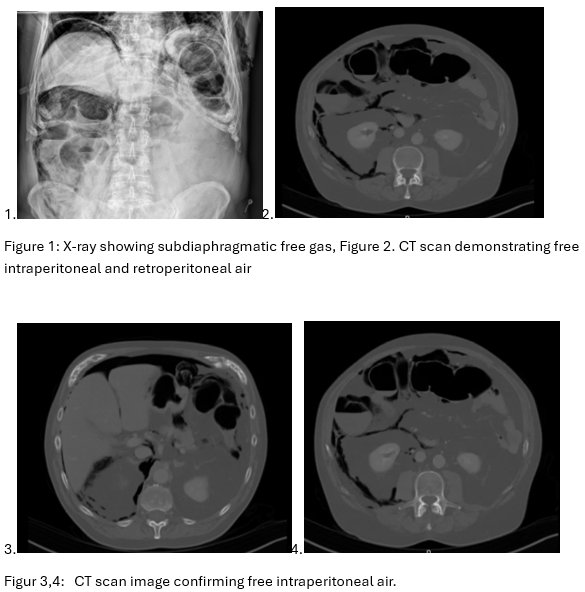

Einleitung: Die European Society of Gastrointestinal Endoscopy (ESGE) veröffentlichte 2017 eine Leitlinie zur Qualitätsverbesserung mit der Festlegung sog. key performance measures (KPMs) (siehe Abb.) mit dem Ziel, die Untersuchungsqualität in Europa durch standardisierte Parameter zu verbessern.

The picture is a graphic describing the key performance measurements from the ESGE guideline 2017: 1. Adequate antibiotic prophylaxis before ERCP (>90%), Bile duct cannulation rate (>90%), Clearance of common bile duct stones (>90%), Stent placement in case of biliary obstruction (>95%), Safety of ERCP (PEP rate <10%)